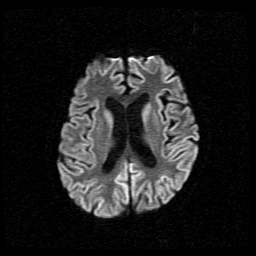

【113-1 醫學(四) 第50題】66歲女性最近一個多月來出現記憶力減退、視幻覺、走路不穩,突然聽見鞭炮聲會身體顫抖。她的腦部磁振造影擴散加權成像(diffusion-weighted imaging)結果如下圖。她最可能的診斷是:

詳解

破題關鍵

本題的解題核心在於結合病患的臨床症狀(快速進展的失智、視幻覺、肌躍症)與腦部磁振造影擴散加權成像(DWI)的典型影像表現。圖片中大腦皮質呈現明顯的亮訊號(hyperintensity),這種「皮質緞帶徵」(cortical ribboning)是診斷庫賈氏症的關鍵視覺線索。